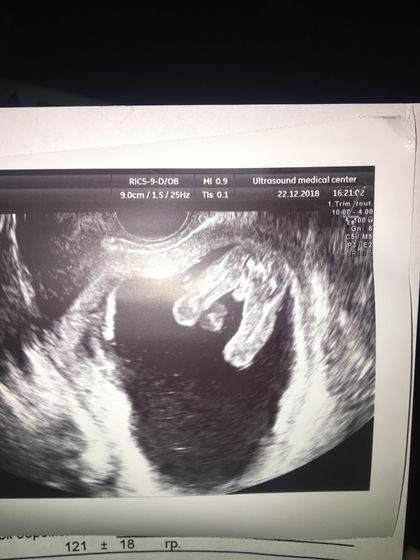

Срок 14-15 недель, на первом скрининге сказали возможно девочка, а в этот раз минут 20 узист пытался разглядеть пол но малыш все время закрывался, и говорит 50/50, вроде и девочка и похож на мальчика. Как считаете кто?)

Да не, если уже такой сформированный бугорок, это уже яички, у девочек к 15 нед бугорок рассасывается

Вот как по мне так тоже мальчик, но врач сказал что на таком сроке у них половые органы практически одинаковые, сказал мошонки нет( хотя этот специалист обычно на 12 неделе с точностью 100% определяет мальчиков)

Мне в 15 недель сказали пол ребёнка, многим девочкам в 12 уже говорят. Все зависит от специалиста и аппарата узи. У вас думаю мальчик )))